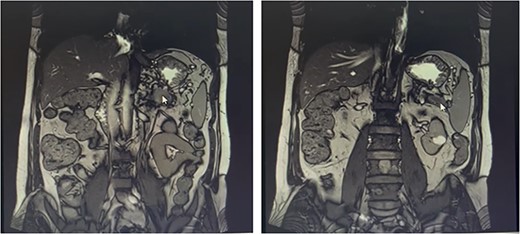

Our patient is a 55-year-old man with a history of rectal adenocarcinoma cancer in the last 2 years. At that time, he presented with flank pain and kidney stones. After examination and diagnostic tests, he was diagnosed with colon cancer that a 12 cm mass was reported and then colectomy surgery was performed. Then six sessions of radiotherapy were considered for him. In the new regression, 2 years after the colectomy surgery, during the examination phase, due to the exacerbation of pain, a computed tomogaphy (CT) scan (Figs 1 and 2) and endoscopy were requested for the patient, in which pancreatic cancer was observed. After that, the patient was placed under endoscopic ultrasound (EUS), which is reported. There was one 35 × 29 mm hypoechoic and round lesion with ill-defined border in pancreatic tail with no involvement of pancreatic duct or splenic vessels in favor of metastasis. EUS fine-needle biopsy with needle 22G was performed. Then the patient underwent a biopsy and the final confirmation was made.

Metastatic masses can be seen in the pancreatic tissue on the CT-Scan (transverse/axial view)

Metastatic masses can be seen in the pancreatic tissue on the CT-Scan (coronal view)

FDG-PET/CT Scan (videos 1 and 2) on abdominal and pelvis reported that calcified granuloma without FDG uptake was seen in the liver segment II. There were two ill-defined foci of increased FDG uptake in the body (metabolic diameter = 26 mm, SUVmax = 7.8) and tail (metabolic diameter = 13 mm, SUVmax = 7.4) of the pancreas gland, persisting on delayed images. Hypermetabolic tumoral lesion in the body and tail of the pancreas are suggestive of metastasis.